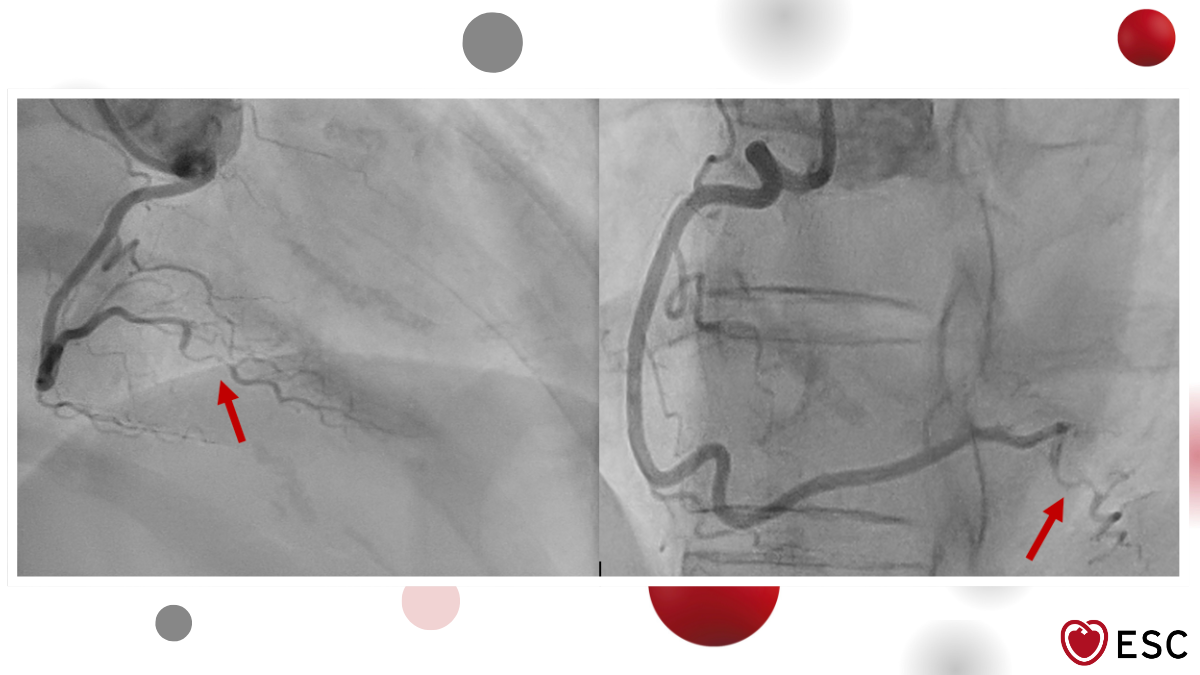

Image of the week 11 February 2026

Doctor Raid Faraj

Doctor Sebastien Hess

Doctor Xavier Lamit